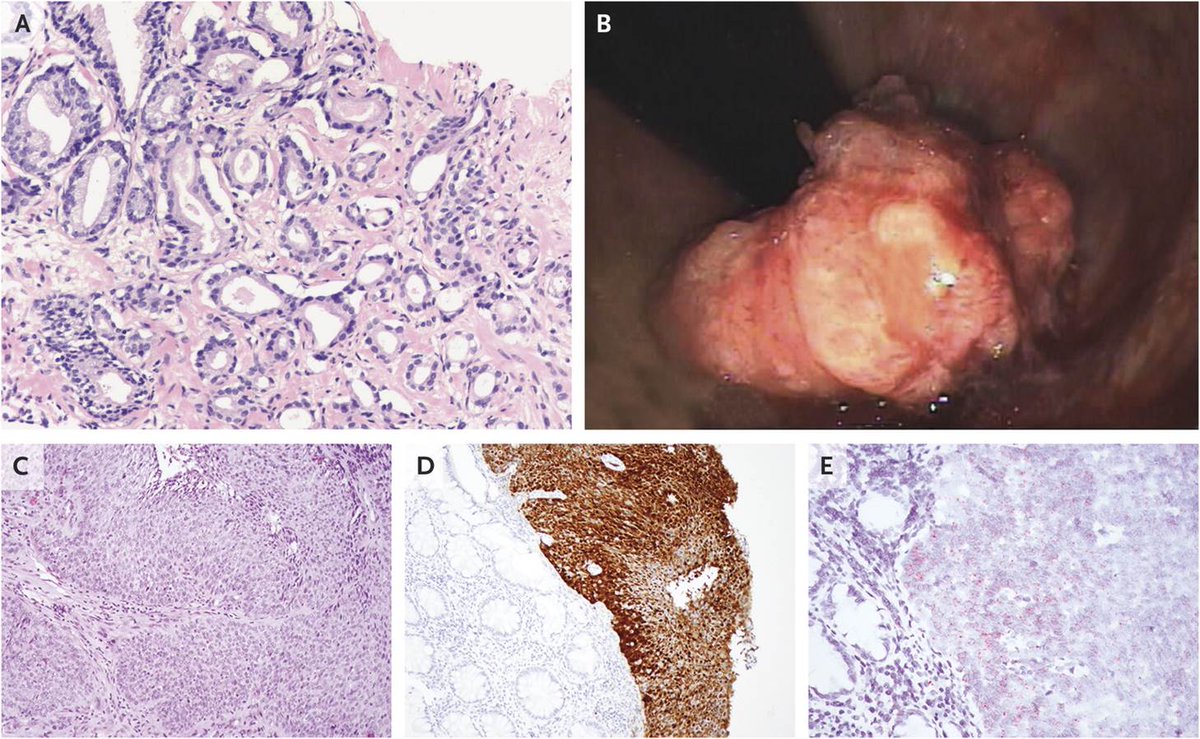

Case Record of the

#MGH: Year-Old Man with Rectal Bleeding and a History of#ProstateCancer http://nej.md/2hamqjr pic.twitter.com/VX3RA4VInT